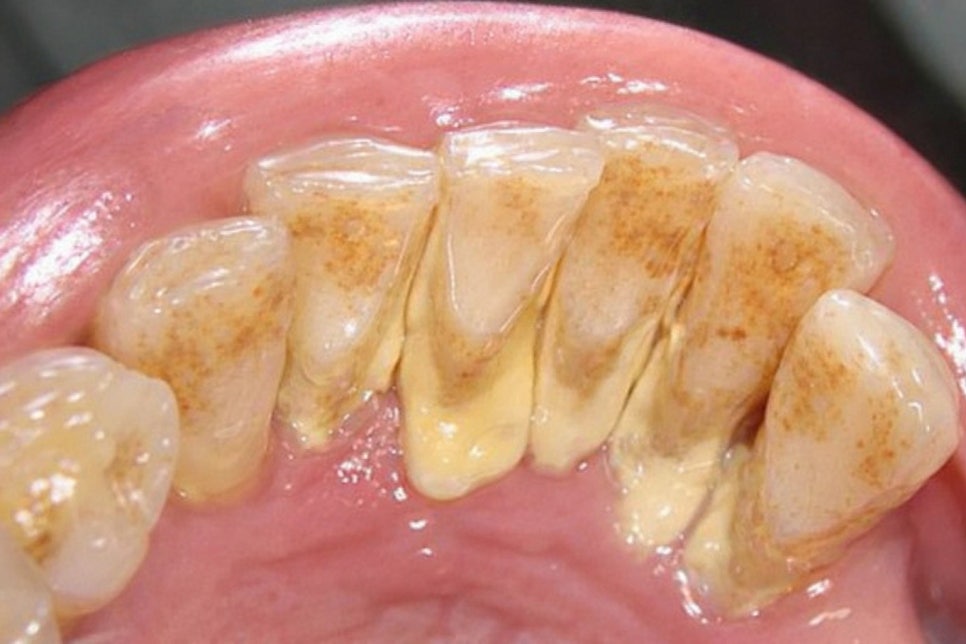

잇몸 위쪽 눈에 보이는 부위에 쌓이는 것을

치은연상치석이라 하며

아래 깊숙한 곳에 형성되는 것을

치은연하치석이라 말합니다.

연상은 침 속 무기질이 치태와 결합하며 만들어지고

색이 비교적 밝으며 육안으로도 확인이 가능합니다.

반면 연하는 색이 짙은 갈색 혹은

검은빛을 띠고 단단하게 굳어있는 것이

큰 특징입니다.

치은 속에 숨어있기 때문에

거울로 볼 수 없으며

칫솔로도 접근하기 어렵습니다.